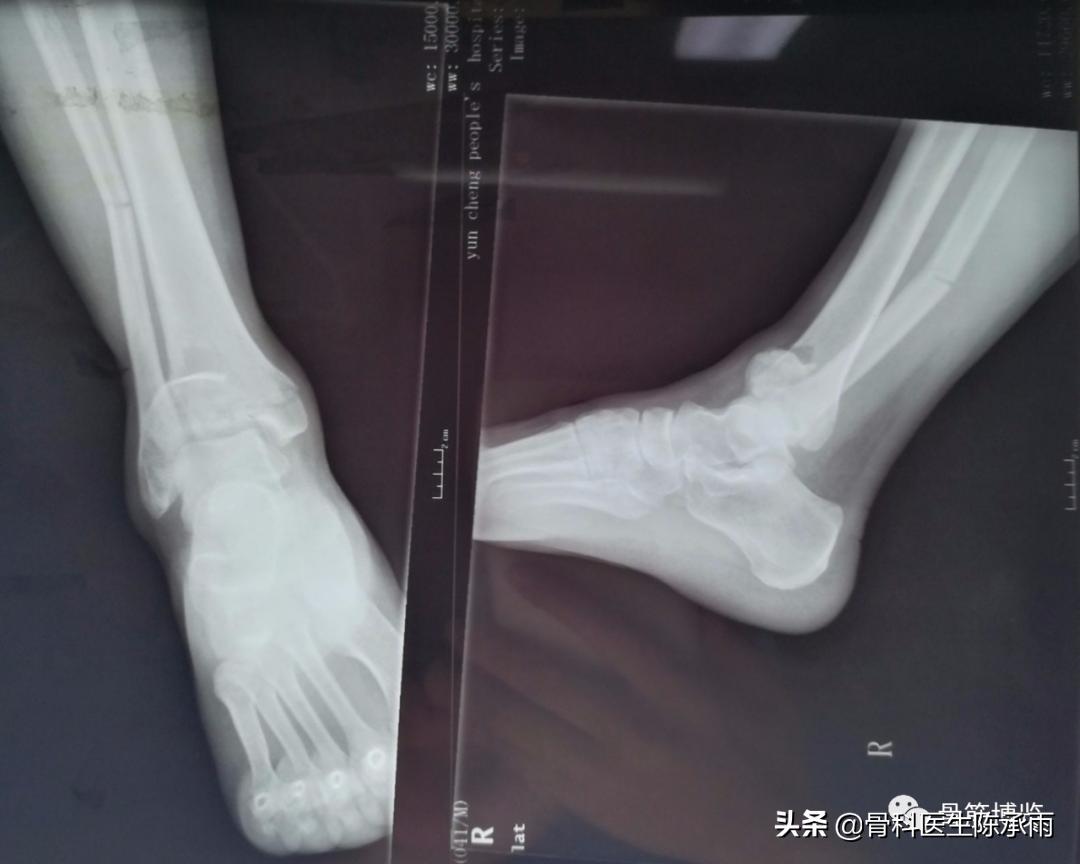

今天下午一台踝关节手术 ,内踝、前踝、后踝和腓骨下段骨折,虽然多见,也做过很多同类和更复杂的,但次手术都有所收获,只求自己的手术技能精益求精。

骨折固定满意。